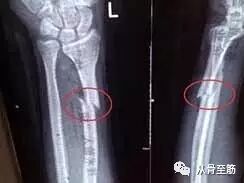

? ? ?第二:内固定取出后,会遗留钉孔,特别是如果取出过程中出现断钉,采用各种办法将断钉取出,钉孔更大,这些钉孔愈合需要时间。在钉孔的局部是力量薄弱区,术后过早负重,可能会因轻微外伤或外力造成骨折。